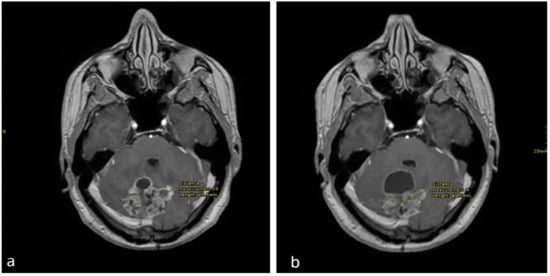

Follow-up MRIs after 6 and 9 months of treatment in December 2017 and March 2018 revealed reductions in the solid components of both the cerebellar and pineal masses, despite an increase in the cystic component and persistent hydrocephalus (Figure 1 and Figure 2). Since the patient was asymptomatic, dexamethasone was discontinued at that point.

Figure 1. Axial enhanced T1 weighted images of the brain at the level of the cerebellum (a), performed in September 2017 and (b) in December 2017. There is an interval decrease in the size of the solid enhancing mass, however there is an increase in the anterior cystic component.